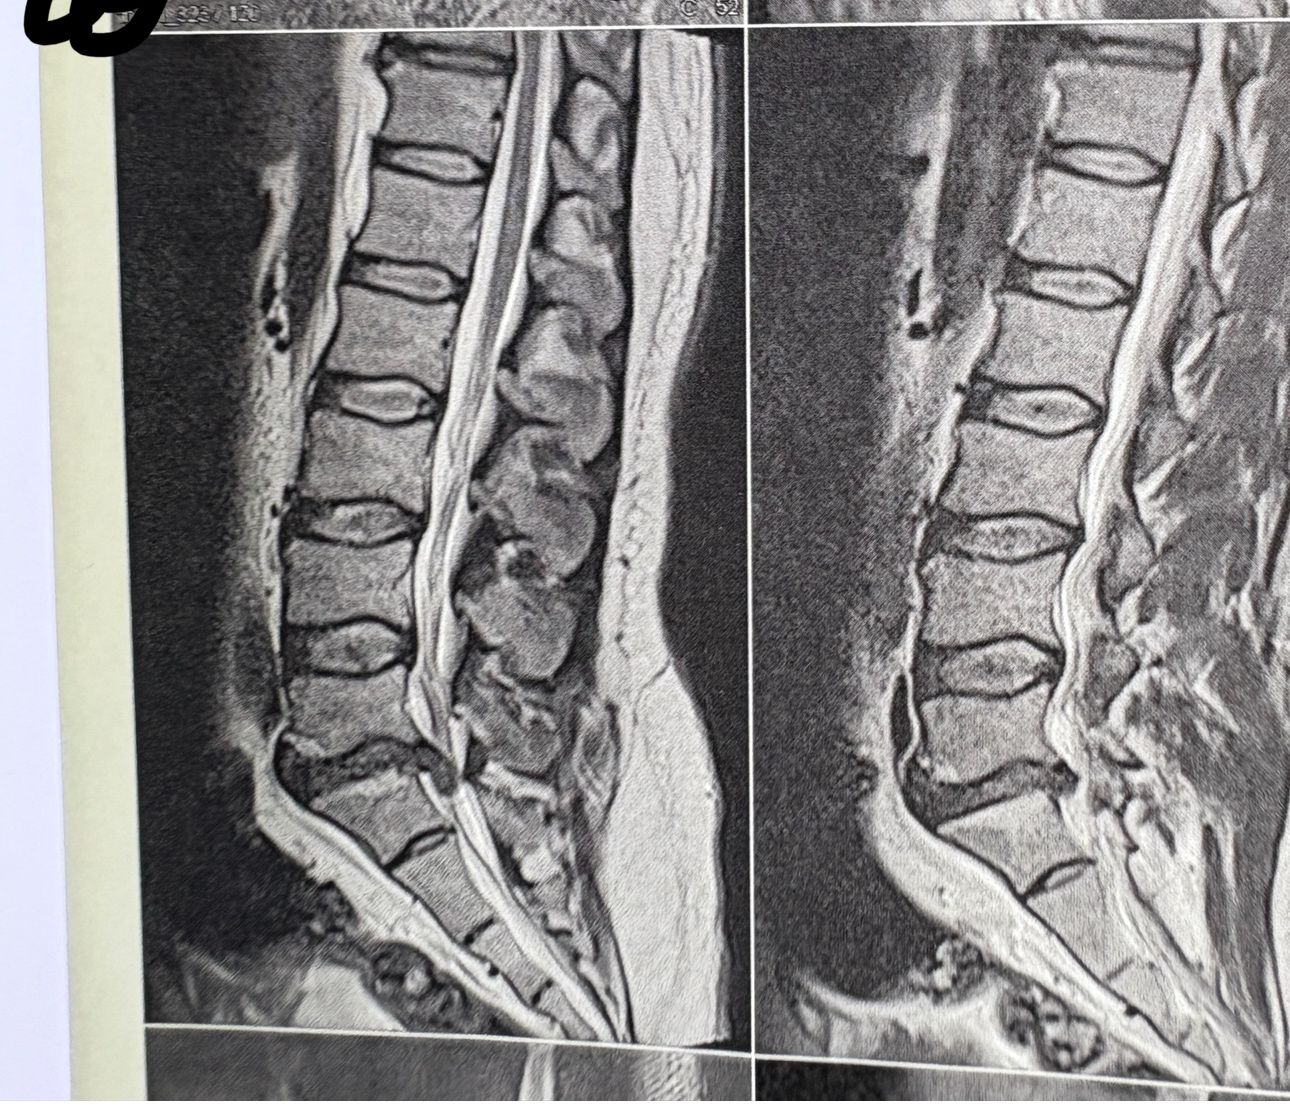

32 years female patient presented to my office one year ago with moderate cervical pain and R. Arm pain ,mild LBP with no radicular pain. Her mri in C/s had few bulges and few segmentsl dysfunctions

Her lumbar mri showed Contained R. Para. L5-S1 extrusion

She got treatment just for her neck and exercises for her low back. Few months later had lumbar disc surgery

Few days ago on may on june 08/2025, presented with severe LBP and no radicular pain

I have post her lumbar MRI before and after surgery. I consulted with a neurosurgeon at our clinic and he said doesn’t need another surgery because doesn’t have radicular pain or neurological deficits

For her pain i have started to do mild decompression by Cox and DTS and acupuncture, no adjustment whatsoever.

Please mention what differences you see before and after surgery